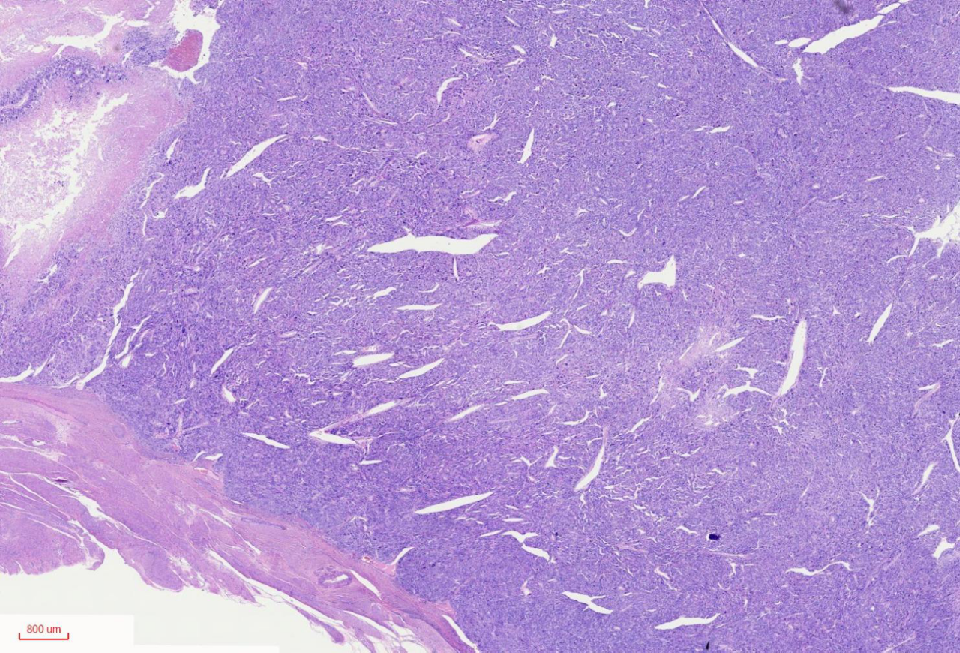

组织学改变

肿瘤与周围境界清楚

肿瘤境界清楚